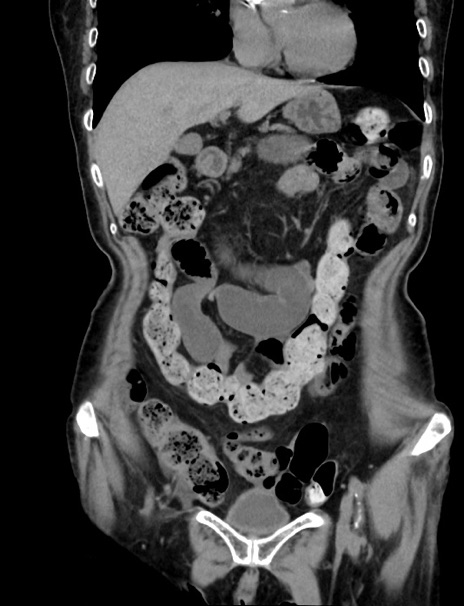

症例33(冠状断像)

【症例】70歳代 女性

【主訴】心窩部痛

【現病歴】延髄病変の精査・加療にて神経内科入院中。本日より心窩部痛あり。

【既往歴】虫垂炎

【身体所見】右下腹部を中心に圧痛と反跳痛あり。

【データ】WBC 10900、CRP 0.02